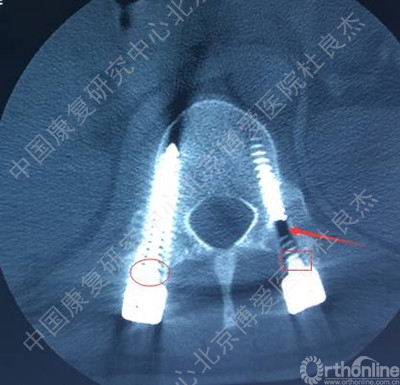

3、胸12椎弓根钉断裂

AO分型,C3型骨折,极度不稳。胸腰段骨折,根据Load–sharimg评分,大于7分,且伴有后方结构破坏,单纯的后路短节段固定稳定性肯定是不行的,内固定失效的可能性较大。建议后方长节段固定+前方植骨融合内固定。

胸腰段椎体骨折脱位出现断钉原因:1.此处骨折脱位除椎体骨折外,附件及韧带等软组织损伤严重。从解刨上看3种因素决定此处是应力集中地。需固定到伤椎上下各2个椎体。2.从影像学可知,胸12腰1似乎过度撑开了。3.从影像学可知,极度不稳,应融合胸12腰1。下一步:去除断钉,延长上方固定到胸10或11并做后路截骨椎间隙植骨。或前路椎间隙植骨融合内固定